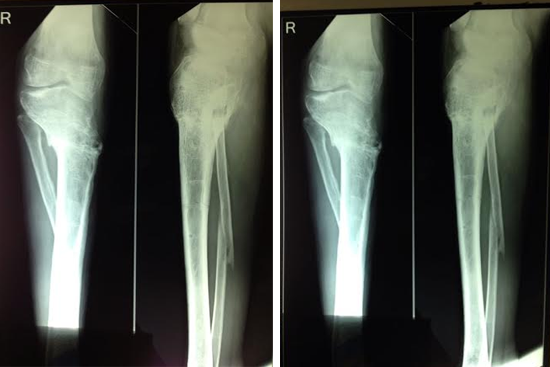

HTO Ilizarov